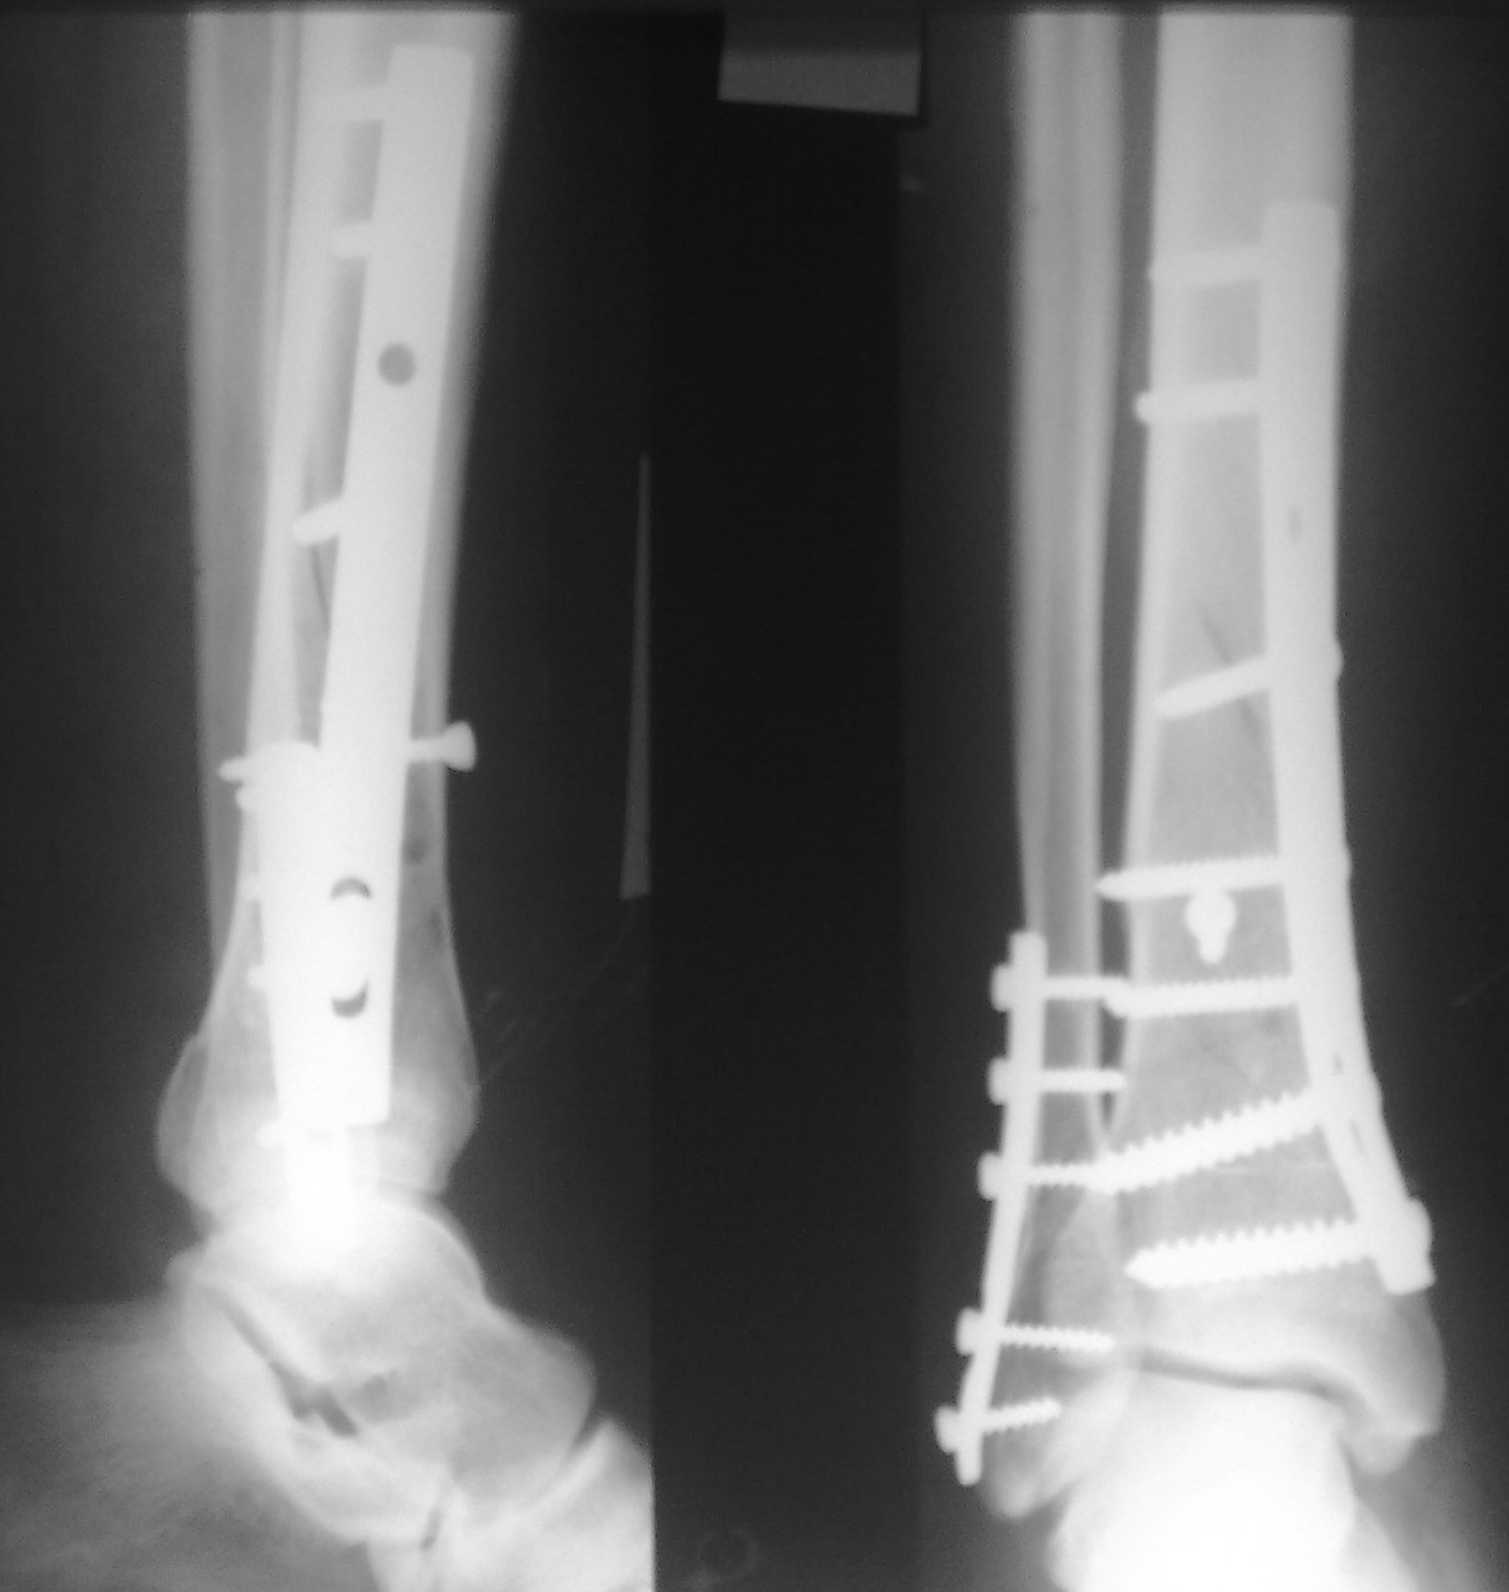

Спасибо за советы. Выполнен МОС обоих костей голени

Lig. tibiofibulare anterius оказалась целой. Был выявлен разрыв межкостной мембраны между берцовыми костями.

Разрыв межкостной мембраны между берцовыми костями был выявлен в зоне оперативного вмешвтельства на малоберцовой кости выше ее перелома. Логично было бы предположить, что он (разрыв) продолжается до проксимального синдесмоза голени. Но передняя межберцовая связка оказалась целой, поэтому ДМС оказался стабилен.

Все более банально - разрыв межкостной мембраны выден на исходном снимке - внимательней рассмотрите расстояние между берцовыми костями выше и ниже места перелома большеберцовой кости - Вам станет это понятно и без МРТ. А интраоперационно на малоберцовой кости пришлось сопоставлять не дистальный отломок к проксимальному, как это обычно приходится делать при переломе лодыжки, а наоборот - проксимальный отломок к дистальному. т.к. проксимальный отломок малоберцовой кости нестабильной из-за разрыва межкостной мембраны.